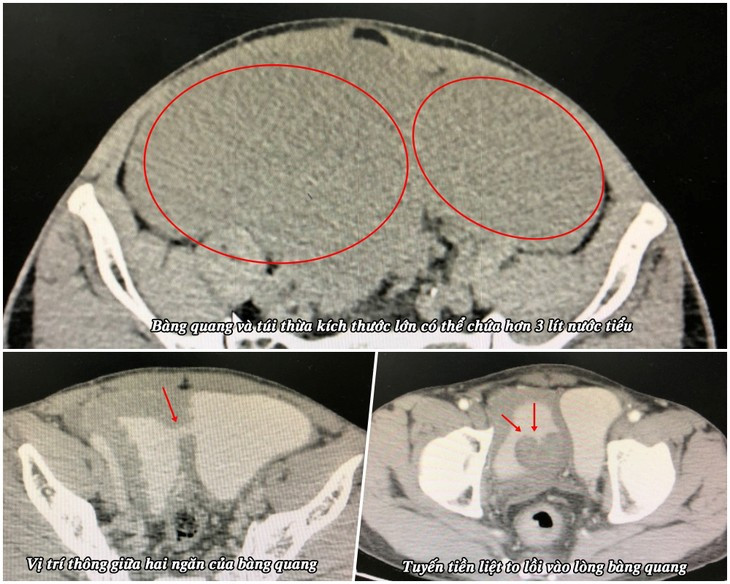

Bệnh nhân là ông Nguyễn Văn T. (58 tuổi) ở huyện Vân Đồn). Ông T. cho biết ở nhà thường thấy bụng dưới to và hay tiểu rắt, sau khi đi tiểu xong vẫn không thoải mái nên đi viện khám. Qua kết quả siêu âm và chụp cắt lớp vi tính phát hiện túi thừa bàng quang kích thước lớn (15 x 20 cm) và tuyến tiền liệt phì đại.

Ca mổ được thực hiện bởi bác sĩ CKII Phạm Việt Hùng, Trưởng khoa Ngoại cùng các cộng sự. Mặc dù bệnh nhân đã đi tiểu trước mổ nhưng khi đặt sond tiểu trong mổ thì số lượng nước tiểu còn dư trong bàng quang và túi thừa lên đến 3200 ml.

Bệnh nhân được phẫu thuật theo đường dưới phúc mạc, kiểm tra thấy bàng quang giãn to và có thông với một túi thừa dung tích lớn ở bên thành trái, tuyến tiền liệt phì đại đẩy vào lòng bàng quang gây đái khó và giãn bàng quang. Các bác sĩ đã tiến hành phẫu tích cắt bỏ túi thừa bàng quang và bóc khối u tuyến tiền liệt. Ca mổ diễn ra thuận lợi sau khoảng 1 tiếng phẫu thuật.

Phim chụp bàng quang và tuyến tiền liệt của bệnh nhân - Ảnh BVCC

Khi phẫu thuật, chúng tôi thấy bàng quang “khổng lồ” của bệnh nhân T. chứa hơn 3 lít nước tiểu, gấp 6 lần dung tích bàng quang bình thường. Ê kíp tiến hành cắt bỏ túi thừa bàng quang và khối u phì đại tuyến tiền liệt, nguyên nhân gây tình trạng này. Ca phẫu thuật thành công giúp người bệnh hết các triệu chứng đau tức bụng, đi tiểu nhiều lần, tiểu không hết, nâng cao chất lượng cuộc sống sinh hoạt về sau”.